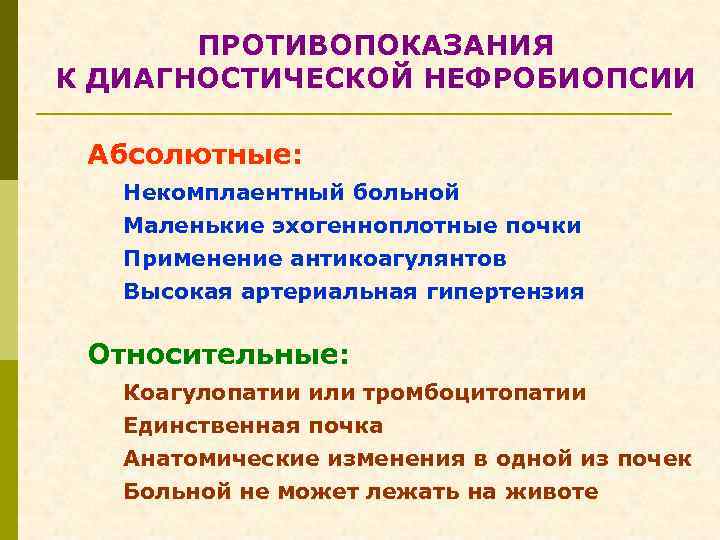

ПРОТИВОПОКАЗАНИЯ К ДИАГНОСТИЧЕСКОЙ НЕФРОБИОПСИИ Абсолютные: Некомплаентный больной Маленькие эхогенноплотные почки Применение антикоагулянтов Высокая артериальная гипертензия Относительные: Коагулопатии или тромбоцитопатии Единственная почка Анатомические изменения в одной из почек Больной не может лежать на животе